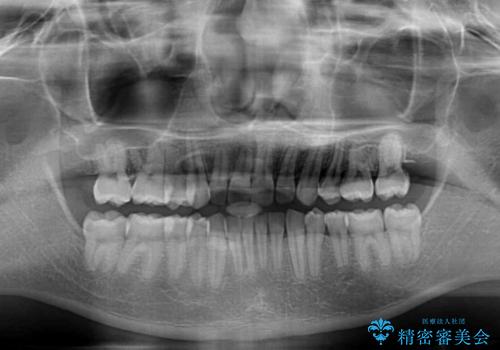

隙間の原因は、埋伏や前後に重なってしまっている上顎小臼歯と、下の前歯が見えなくなるくらいのディープバイトで、それらを改善する必要がありました。

アンカースクリューを用いて下に位置している上顎前歯を持ち上げるとともに、ワイヤー装置によりディープバイトの原因である奥歯の傾斜を改善することで、矯正治療を行っていくこととしました。

また、矯正治療に際し、4本全ての親知らずと、埋もれている右上小臼歯を事前に抜去することとしました。

顕著なディープバイトのため、頻繁に装置が脱離することがあり、治療期間が想定よりも長くかかることがありますが、当初の予定期間で無事に治療を終えることができました。